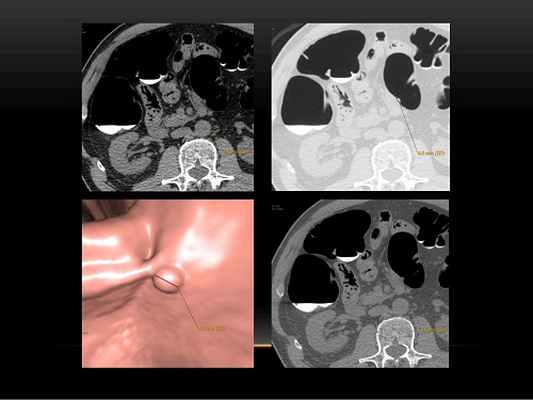

Виртуальная колоноскопия — проводится с двойным контрастированием (пероральный прием контраста и его внутривенное введение при необходимости). Осмотр толстой кишки до самых нижних отделов малого таза, включая прямую кишку, методом компьютерной томографии позволяет определить:

Полип кишечника на широком основании, выявленный на виртуальной (КТ) колоноскопии. Исследование выполнено врачом лучевой диагностики КГНЯ Петровой М.А.